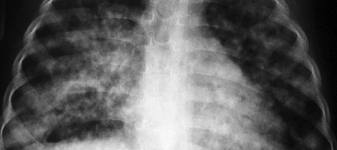

بمناسبة اليوم العالمي للدرن والذي يحل في 24 مارس من كل عام ( الموافق 1 / 5 / 1433 من هذا العام) أقدم هذه النشرة المختصرة للإخوة والأخوات الزملاء والزميلات راجيا أن تعم بها الفائدة والله الموفق . مرض الدرن ( السـل ) [align=center] ما هو الدرن؟ [/align]الدرن (السل) هو أحد الأمراض المعدية المزمنة التي قد يتعرض الإنسان أو الحيوان للإصابة بها , وينشأ نتيجة الإصابة بميكروب الدرن . [align=center] أنواع الإصابة بالدرن: [/align] 1– الدرن الرئوي . 2 – الدرن خارج الرئة: ويصيب الأعضاء خارج الرئة مثل:الغدد الليمفاوية – العظام – الجهاز العصبى – الحنجرة - القناة الهضمية – العين – الجلد . [align=center] ميكروب الدرن: [/align] هناك نوعان من ميكروب الدرن: 1- ميكروب الدرن البشري (أكثر من 99% من الحالات) . 2- ميكروب الدرن البقري (أقل من 1% من الحالات) . [align=center]طرق العـدوى:[/align] 1 – يمثل الجهاز التنفسى المصدر الرئيسى للعدوى بالدرن وينتقل الميكروب إلى الجهاز التنفسى عن طريق استنشاق قطيرات رذاذ المريض المحملة بالميكروب والناشئة عن سعال المريض بالدرن أو عطاسه , وكذلك عن طريق تدخين الشيشة عندما يكون أحد المدخنين مصاباً بالدرن . 2 – قد ينتقل الميكروب إلى اللوزتين أو القناة الهضمية عن طريق شرب لبن ملوث مصدره أبقار مصابة بالدرن أو تناول منتجات ألبان ملوثة بالميكروب . [align=center]عوامل زيادة احتمالات الإصابة بالمرض:[/align] 1– مخالطة المرضى المصابين بالدرن الرئوى النشط . 2– الازدحام وتلوث البيئة وسوء التهوية . 3– الفقر وانخفاض مستوى المعيشة . 4– الجهل وعدم إتباع التعليمات الطبية للوقاية من المرض . 5 – بعض الأمراض تزيد من احتمالات الإصابة بالدرن مثل: البول السكرى ، الفشل الكلوى ، مرض نقص المناعة المكتسبة (الأيدز) ، العلاج لفترات طويلة بمركبات الكورتيزون ، بعض الأمراض الخبيثة مثل سرطان الدم . ما هو الفرق بين الإصابة بالميكروب ومرض الدرن؟ • تختلف الإصابة بميكروب الدرن عن حدوث مرض الدرن ، لأن معظم الذين يصابون بميكروب الدرن لا تظهر عليهم أعراض المرض ولا تتحول الإصابة لديهم إلى مرض . ويعتبر المرض موجودا إذا اشتكى المريض من أعراض المرض وأمكن اكتشافه بوسائل التشخيص مثل فحص الأشعة أو الفحص المعملى للبصاق أو غيره من العينات . ما هى أعراض المرض؟ • أعراض عامة : وهى ارتفاع فى درجة الحرارة ، عرق ليلى ، فقدان الشهية ونقص الوزن . • أعراض رئوية وهى سعال ، بصاق مدمى (بصاق معرق بالدم أو دماً صريحاً) ، ألم بالصدر نتيجة التهاب الغشاء البلورى . • قد يشكو المريض من ضيق التنفس نتيجة الانسكاب البلورى الدرنى ، الالتهاب الرئوى الدرنى ، الكهوف الدرنية ، الالتهاب الشعبى الدرنى . كيف يمكن تشخيص الدرن الرئوى؟ • 1 – الفحص الإكلينكى . • 2 – الفحص بالأشعة . • 3 – الفحص المعملى لميكروب الدرن فى البصاق وعينات أخرى . • 4 – فحص الدم . • 5 – اختبار التيوبركولين ( اختبار عن طريق الجلد ). [align=center]كيف يمكن علاج الدرن؟[/align] تستخدم عدة أدوية معا لعلاج الدرن (قد يصل عددها إلى خمسة أو أكثر) ولمدد طويلة (من ستة أشهر إلى سنتين أو أكثر ) ولابد من الالتزام بجرعات الأدوية والمدة التي يحددها الطبيب كي لا تنتكس الحالة أو تكتسب الميكروبات مناعة ضد الأدوية , وأحيانا تستدعي بعض الحالات التدخل الجراحي إلى جانب الأدوية , ولقد قامت الحكومة السعودية مشكورة بتوفير علاج الدرن مجانا للمواطنين والمقيمين . التطعيم ضد الدرن: يستخدم لقاح الدرن (بى.سى.جى) فى تطعيم حديثى الولادة عادة عند عمر شهر كذلك يستخدم – فى الأشخاص ذوي اختبار سلبى للتيوبركولين إذا كانوا أكثر تعرضاً للإصابة بالميكروب نتيجة مخالطة المرضى بالدرن . ( مع أطيب التمنيات لكم ولسائر المسلمين بدوام الصحة والعافية ) التعديل الأخير تم بواسطة أحمد صلاح الحفني ; 2014-03-30 الساعة 10:51 PM. |